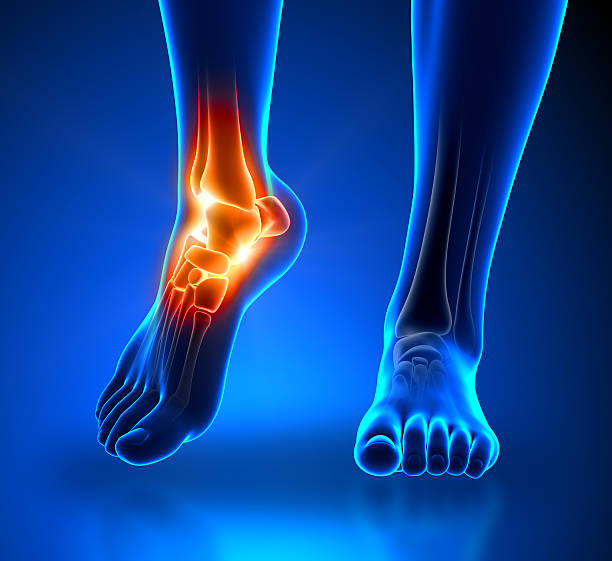

발뒤꿈치가 아픈 이유 2. 아킬레스건염

발뒤꿈치가 아픈 이유 두 번째는 아킬레스건염입니다. 아킬레스건염은 아킬레스건 부위가 반복적으로 미세한 손상을 입으면서 생기는 통증으로 이 역시 발뒤꿈치 통증을 유발합니다.

아킬레스건염 역시 뒤꿈치 혹은 발바닥에서 주로 통증이 느껴지며 특히 아킬레스건 부위가 부어오르며 움직임을 가져간 이후에는 종아리에서부터 발뒤꿈치까지 통증이 심하게 나타나고 이러한 증상이 지속되면 무플, 고관절, 허리에까지 무리가 갈 수 있기 때문에 족저근막염과 마찬가지로 빠른 치료를 받는 것이 중요합니다.